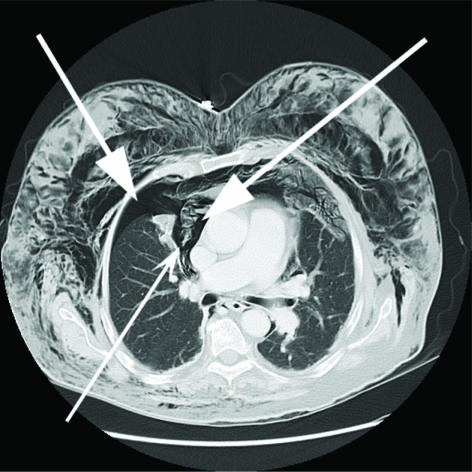

Figure 1.

Axial CT scan of the chest demonstrating pneumomediastinum and a right pneumothorax (large arrows). Note communication between both (thin arrow).